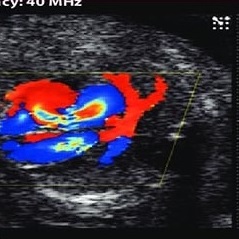

سونوگرافی کالر داپلر

همه چیز در مورد سونوگرافی داپلر رنگی